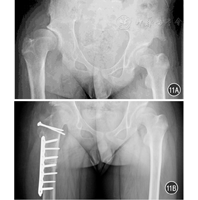

8岁以上大龄髋关节脱位处理极为棘手。对于双侧脱位患者肢体平衡,仅有鸭步和腰椎前凸,无痛情况下自身髋关节可以使用很长时间,故不建议手术干预。但单侧髋关节脱位将合并严重的肢体不等长、跛行、继发脊柱侧凸、继发膝外翻等严重并发症,可以考虑积极处理。既往采用假臼造盖、Chiari骨盆内移截骨等方法治疗,长期效果不很理想[28]。新近采用的骨盆支撑截骨术治疗,虽然能够取得一定效果,但长期疗效欠佳,并给后期全髋关节置换造成较大的困难[29,30]。2012年,Ganz等[31]通过SHD对Colonna关节囊成型手术进行改良,部分患者取得了长期的"几乎正常"的临床效果。

改良Colonna关节囊成型的技术要点包括:通过SHD显露髋关节,保护股骨头血运;将关节囊从髋臼缘完整分离,修整后完整包裹股骨头;在真性髋臼部位磨挫制作髋臼至适当大小;将股骨头还纳,维持在稳定位置;必要时进行Stahli造盖、股骨颈相对延长、股骨短缩/去旋转截骨。见图10、图11。该手术操作复杂,技术要求很高,康复时间长,并发症较多,短期内谨慎开展。